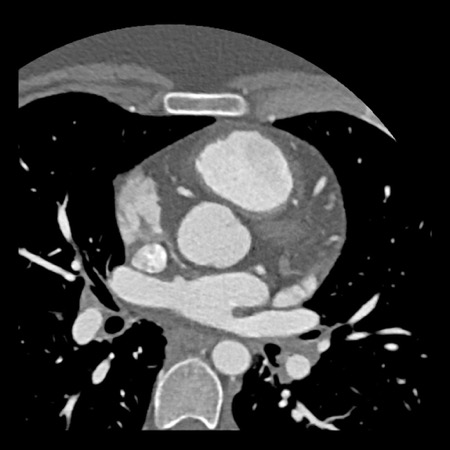

case 2 – CAD-RADS 5/P2/S

First, scroll through the CTA images.

How would you describe the findings on the coronary CTA?

The findings are:

- Stent in the mid

LAD with low-attenuation within the stent suggestive of minimal in-stent

restenosis (<25%). Non-calcified plaque distal to the stent

causing mild stenosis (25-49%). Notice bridging on a short segment in

the distal LAD. - Non-calcified

plaque in the LCX causing mild stenosis (25-49%). - Occlusion of the

proximal OM1 branch with distal filling. - Calcified and

non-calcified plaques in the proximal RCA causing mild (25-49%) stenosis. - Total plaque burden

is moderate based on SIS (four segments including proximal RCA, mid LAD, prox

LCX and OM1).

Due to the occlusion of OM1 branch and presence of the stent, this case

reads as CAD-RADS 5/P2/S, which means that this patient needs further

diagnostic workup.